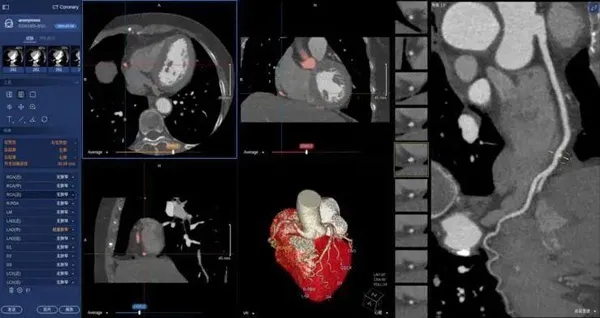

在醫(yī)學領域,機器視覺主要用于醫(yī)學輔助診斷。首先采集核磁共振、超聲波、激光、X射線、γ射線等對人體檢查記錄的圖像,再利用數(shù)字圖像處理技術、信息融合技術對這些醫(yī)學圖像進行分析、描述和識別,最后得出相關信息,對輔助醫(yī)生診斷人體病源大小、形狀和異常,并進行有效治療發(fā)揮了重要的作用。不同醫(yī)學影像設備得到的是不同特性的生物組織圖像,如X射線反映的是骨骼組織,核磁共振影像反映的是有機組織圖像,而醫(yī)生往往需要考慮骨骼有機組織的關系,因而需要利用數(shù)字圖像處理技術將兩種圖像適當?shù)丿B加起來,以便于醫(yī)學分析。